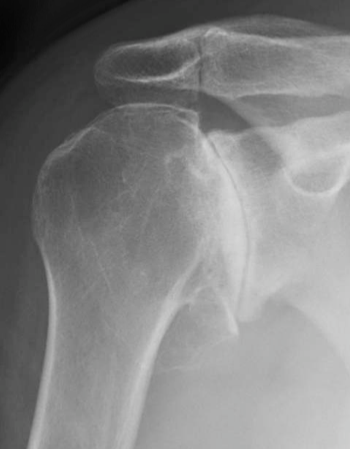

It seems at least equally likely that the observation that the CSA is higher in patients with cuff tears is due to the fact that when the cuff is deficient the humeral head rides up, eroding the superior lip of the glenoid and causing laterally extending spurs on the acromion, both of which would increase the CSA. So the presence of a cuff tear may cause the change in the CSA rather than the other way around. See these examples:

It also seems likely that the observation that the CSA is lower in patients with osteoarthritis is due to the fact that OA results in medial erosion of the inferior lip of the glenoid, which would reduce the CSA. So the OA may cause the change in CSA rather than the other way around. See these examples: